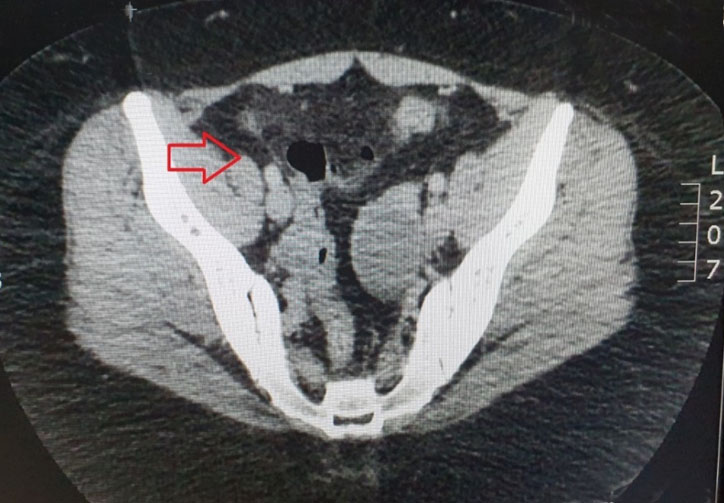

A pelvic ultrasound was done which revealed a possibility of a bicornuate uterus and a 4.4 cm mass seen within left ovary which is hypoechoic in nature which probably represent endometrioma (Figure 1). There was no free fluid noted or any adnexa mass seen. The appendix was not visualized. Due to her nonresolving abdominal pain, a CT scan of abdomen and pelvis was done. It was noted on the scan that there was an inflammatory change in the distal ileum with the appendix being slightly dilated at 6.3 mm and could suggest an early appendicitis (Figure 2 and Figure 3). Apart from the left ovary cyst there were no other abnormalities noted.

Figure 3: Coronal view of the CT scan: red arrow indicates the slightly dilated appendix at 6.3 cm with inflammatory changes in the distal ileum.